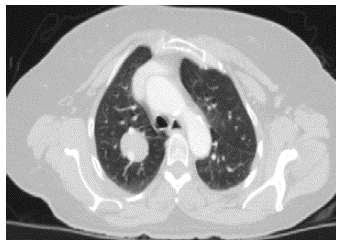

Paciente femenina de 64 años, con antecedentes de hipertensión arterial, bloqueo de rama izquierda, diabetes mellitus no insulinorequiriente y dislipidemia con adecuado control, que consulta con cuadro clínico consistente en dolor torácico inespecífico e intermitente, en hemitórax derecho, de larga data y sin manejo específico, que se exacerba posterior a caída desde su propia altura, asociándose a tos no productiva. Se realiza tomografía computarizada (TC) de tórax con contraste donde se observa un nódulo en el lóbulo superior derecho, de 30 x 26 mm, con bordes bien definidos y atenuación de tejidos blandos, sin captación del medio de contraste; adicionalmente, se encontró un drenaje anómalo de la vena pulmonar superior derecha (figuras 1 y 2).

El diagnóstico suele ser imagenológico. La radiografía de tórax muestra una opacidad redonda, homogénea, bien definida. La tomografia computarizada confirma el hallazgo de una lesión pulmonar redonda u ovoide, bien delimitada, raramente calcificada, con o sin atelectasia o neumonía postobstructiva 8.